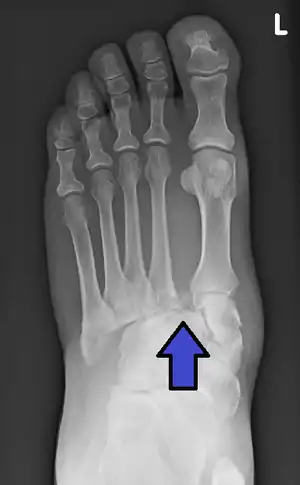

An X-ray of a Lisfranc injury

In a high energy injury to the midfoot, such as a fall from a height or a motor vehicle accident, the diagnosis of a Lisfranc injury should, in theory at least, pose less of a challenge. There will be deformity of the midfoot and X-ray abnormalities should be obvious. Further, the nature of the injury will create heightened clinical suspicion and there may even be disruption of the overlying skin and compromise of the blood supply. Typical X-ray findings would include a gap between the base of the first and second toes.[8] The diagnosis becomes more challenging in the case of low energy incidents, such as might occur with a twisting injury on the racquetball court, or when an American Football lineman is forced back upon a foot that is already in a fully plantar flexed position. Then, there may only be complaint of inability to bear weight and some mild swelling of the forefoot or midfoot. Bruising of the arch has been described as diagnostic in these circumstances but may well be absent.[9] Typically, conventional radiography of the foot is utilized with standard non-weight bearing views, supplemented by weight bearing views which may demonstrate widening of the interval between the first and second toes, if the initial views fail to show abnormality. Unfortunately, radiographs in such circumstances have a sensitivity of 50% when non-weight bearing and 85% when weight bearing, meaning that they will appear normal in 15% of cases where a Lisfranc injury actually exists.[10] In the case of apparently normal x-rays, if clinical suspicion remains, advanced imaging such as magnetic resonance imaging (MRI) or computed tomography (CT scan) is a logical next step.[11]